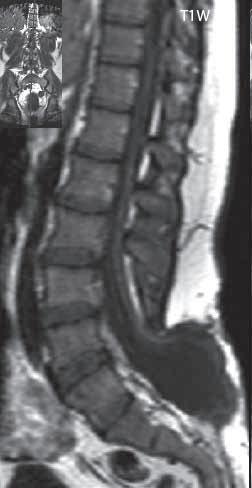

II.6 Vývojové vady míchy a páteře . . . . . . . . 426

II 6 1

Hydrosyringomyelie

Syndrom zadržené míchy a ztluštělého filum terminale (tethered spinal cord syndrome)

426